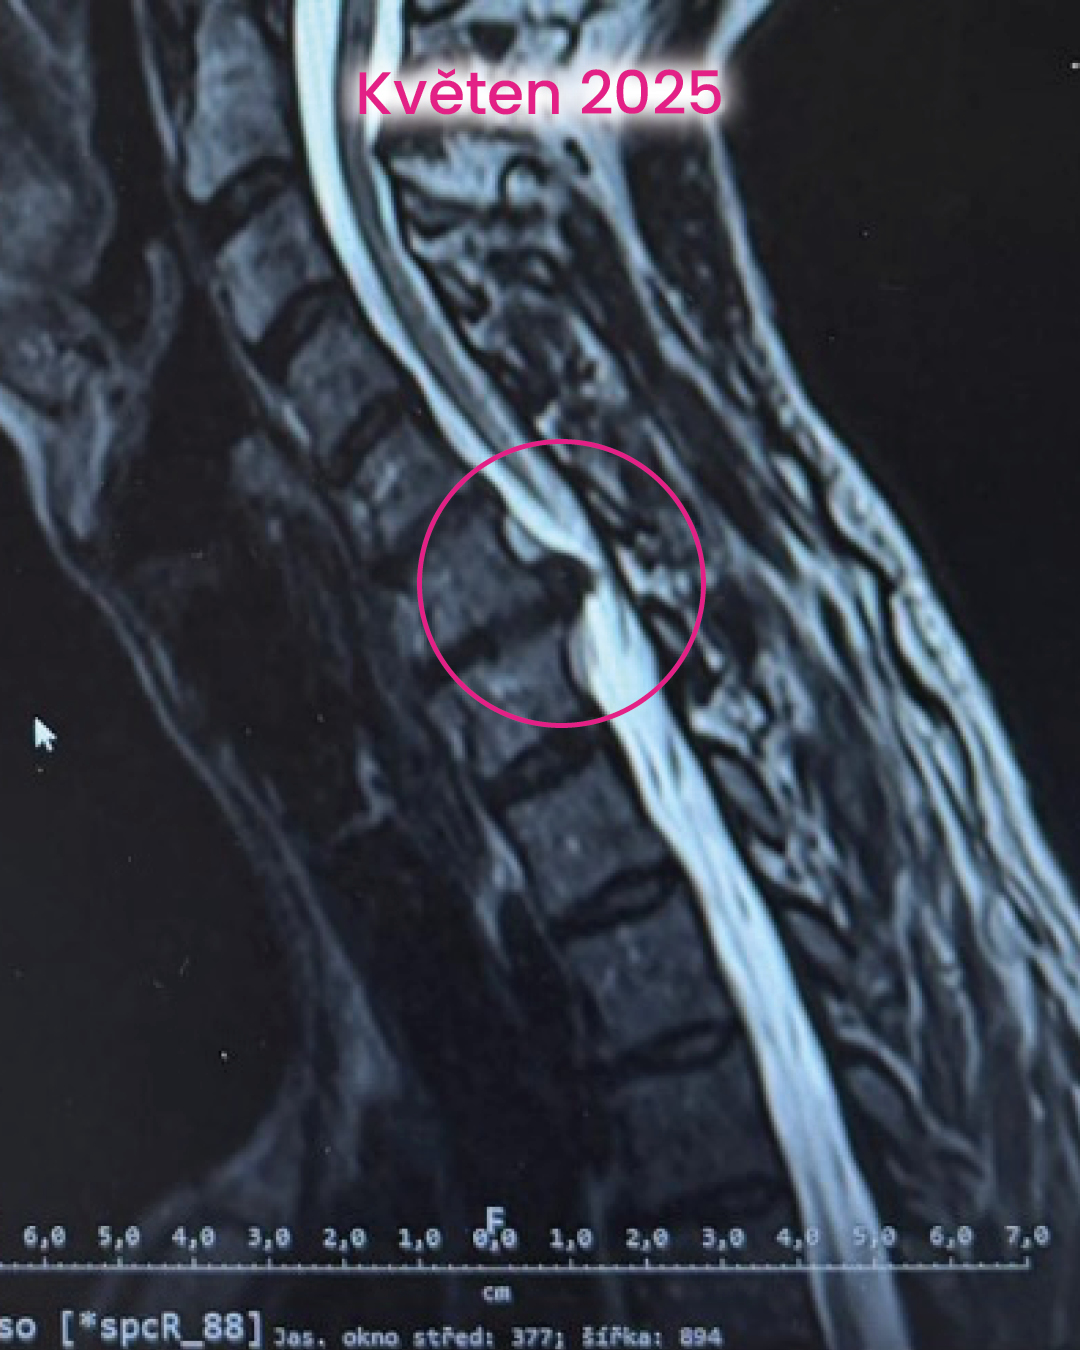

Na začátku to byl typický obraz výhřezu krční ploténky. Ploténka se posune nebo poškodí a začne tlačit na nerv. Výsledkem je kombinace bolesti, brnění a postupně i omezení funkce. Problém ale většinou není jen v samotné ploténce. Ta je spíš důsledkem toho, jak dlouhodobě funguje celé tělo.

Vstupní vyšetření tomu odpovídalo. Bylo vidět výrazné přetížení v oblasti krční páteře a celkovou nerovnováhu. Tělo nebylo schopné rozložit zátěž, takže ji kumulovalo právě tam, kde ji zvládá nejméně. Krční oblast byla přetížená, nervový systém ve vysokém napětí a problém se už promítal dál do těla. Svalová mapa ukázala totéž. Trapézy, šíje, lopatky… ale i střed těla. Tělo bylo v permanentním obranném režimu